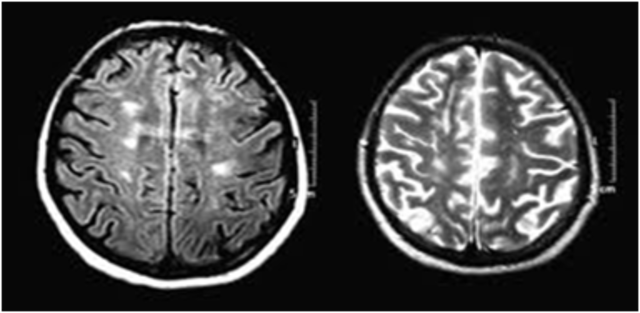

el avance más reciente en RMN, incluye el desarrollo del contraste intravenoso y técnicas rápidas de escaneo